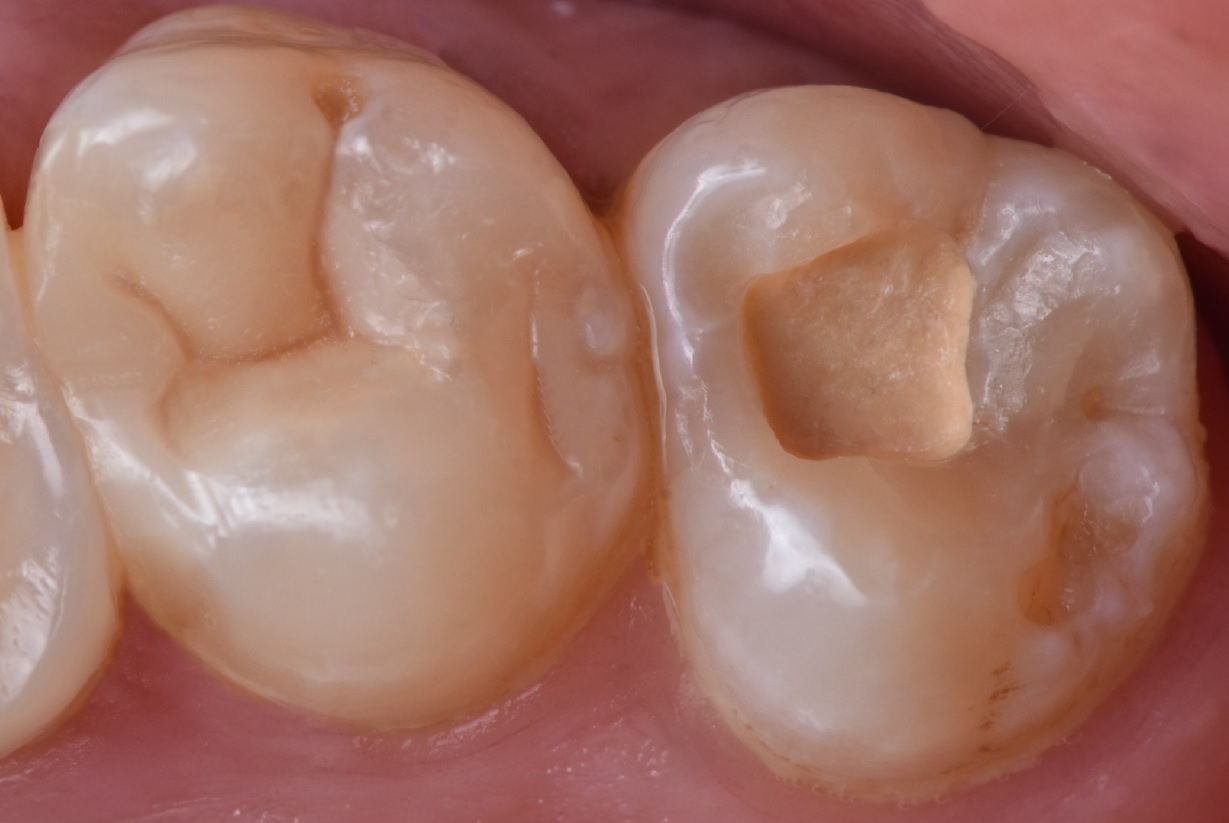

Εικ. 5: Μια κοιλότητα Ομάδος Ι είναι πιο επιθετική στην αφαίρεση όλου του κατεστραμμένου ιστού σε σύγκριση με μια κοιλότητα Ομάδος II και μπορεί να προκαλέσει μεγαλύτερη ευαισθησία. Για να αξιολογηθεί η διατήρηση της ζωτικότητας του πολφού στον τρίτο γομφίο, ο οποίος ήταν ο πιο επηρεασμένος, εφαρμόστηκε το Biodentine XP χρησιμοποιώντας μια τεχνική biobulk-fill, γεμίζοντας πλήρως την κοιλότητα μέχρι την μασητική επιφάνεια ως προσωρινή αποκατάσταση. Αυτή η προσέγγιση επιτρέπει την αναβολή της οριστικής αποκατάστασης, διασφαλίζοντας παράλληλα την σωστή έμφραξη της κοιλότητας για την αποφυγή επιμόλυνσης. Επιπλέον, επιτρέπει την αξιολόγηση της διατήρησης της ζωτικότητας του πολφού και καθορίζει αν απαιτείται ενδοδοντική θεραπεία αν τελικά δεν διατηρηθεί η ζωτικότητα.

Εικ. 9: Το τελικό αποτέλεσμα της αποκατάστασης Ομάδος II στον δεύτερο γομφίο μετά τη χρήση της τεχνικής Essential Lines για τη διαμόρφωση της μορφολογίας του μασητικού επιπέδου.

Εικ. 10: Το τελικό αποτέλεσμα αμέσως μετά την αφαίρεση του ελαστικού απομονωτήρα. Στη συνέχεια, ελέγχθηκε η σύγκλειση και η αποκατάσταση σύνθετης ρητίνης στιλβώθηκε.

Εικ. 11: Ο ασθενής επέστρεψε μετά από ένα μήνα για να ολοκληρώσει την αποκατάσταση. Η ευαισθησία στο κρύο είχε εξαφανιστεί και τα δύο δόντια ανταποκρίθηκαν θετικά στο τεστ ζωτικότητας. Γι αυτό πραγματοποιήθηκε άμεση αποκατάσταση σύνθετης ρητίνης στον τρίτο γομφίο.